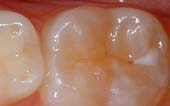

Your pediatric dentist may also recommend protective sealants or home

fluoride treatments for your child. Sealants can be applied to your child’s

molars to prevent decay on hard to clean surfaces.

A sealant is a clear or shaded plastic material that is applied to the chewing surfaces (grooves) of the back teeth (premolars and molars), where four out of five cavities in children are found. This sealant acts as a barrier to food, plaque and acid, thus protecting the decay-prone areas of the teeth.

![]() Before Sealant Applied |

![]() After Sealant Applied |